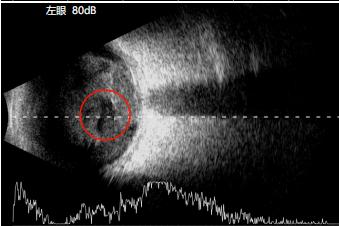

在取得老李同意后立即启动绿色通道。当天急诊为他实施左眼玻璃体切除手术,术中探查发现老李是因为外伤导致左眼隐匿性巩膜裂伤,没有得到及时治疗,引发的感染性眼内炎。历经3小时仔细操作,术中清除眼内化脓组织,注入硅油支撑视网膜,并注射万古霉素抗感染。

玻璃体切割手术中使用3D显微镜的OCT查看视网膜